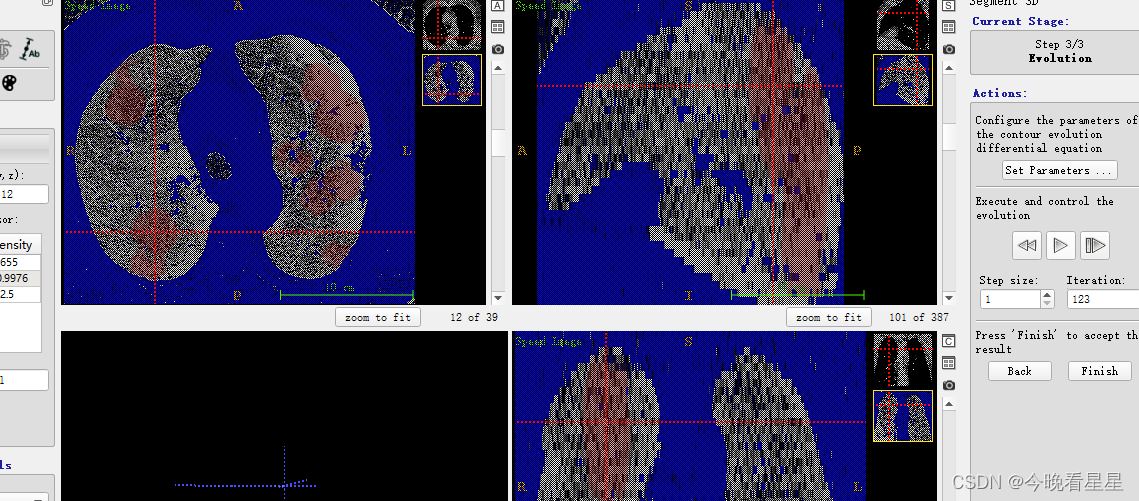

- 观察到区域在不断的扩散

- 3D的结果